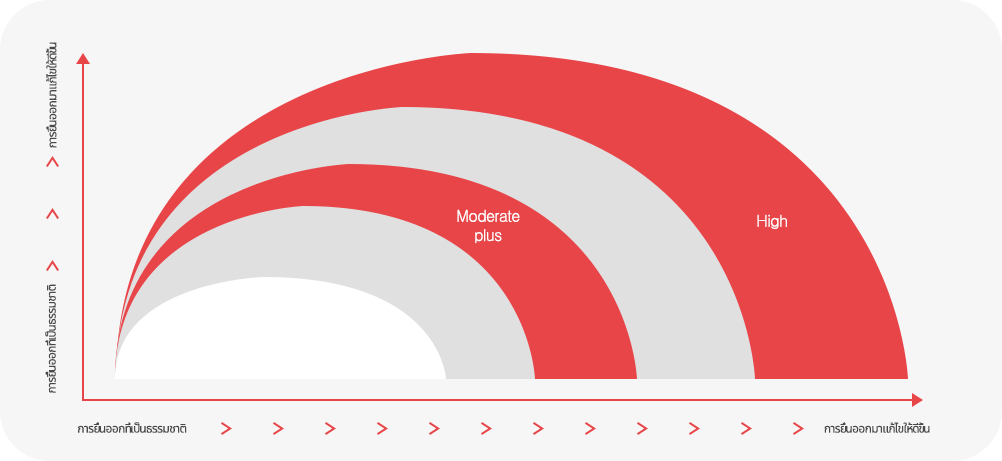

ขนาดที่กำหนดเองสำหรับลูกค้า MINI, DEMI, FULL, CORSE ให้เหมาะกับรูปร่างและหน้าอกของแต่ละคน

ขนาดของการเสริมที่เหมาะสมที่สุด ทำให้สามารถเลือกขนาดผ่านการให้คำปรึกษาที่มีความพึงพอใจมากขึ้น